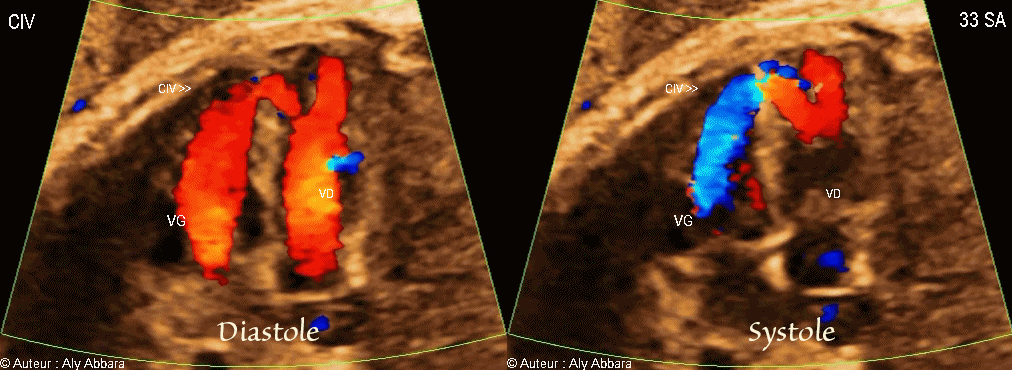

Communication interventricualire (CIV) musculaire, trabéculée et apicale, isolée - foetus de 33 SA

Vidéo et image animée échographiques cardiaques avec Doppler-couleur montrant une malformation cardiaque congénitale isolée ; il s'agit d'une communication interventriculaire (CIV) musculaire, trabéculée et apicale.

Cette CIV musculaire apicale est de moins de 3 mm de largeur, située à l'extrême pointe de ventricule gauche, isolée, sans autre anomalie morphologique ou fonctionnelle cardiaque décelée lors de cette examen.

Le Doppler couleur montre un flux sanguin bidirectionnel sur cette communication interventriculaire apicale.

Fœtus âgé de 33 SA.